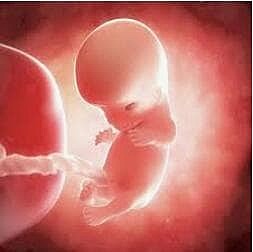

• 51-58 DÍAS – OCTAVA SEMANA

51-58 DÍAS – OCTAVA SEMANA

Aún es visible la cola del embrión.

Los ojos están abiertos y se logra percibir los pabellones auriculares.

Los dedos están unidos a una membrana.

Los parpados se juntan.

Comienza a diferenciarse los genitales externos.

Desaparece la membrana de los dedos.

El embrión ya tiene características humanas más evidentes.